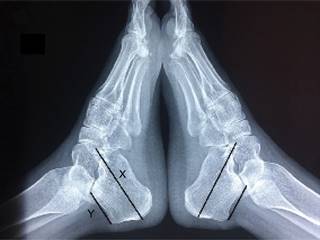

Por otra parte, la deformidad de Haglund es una alteración en la morfología del calcáneo que forma una prolongación ósea vertical en la tuberosidad posterosuperior. Se han propuesto varios criterios de medida para diagnosticarla, el método más usado es el de las líneas de inclinación paralelas (parallel pitch lines);2 recientemente se ha implementado una nueva medición denominada “longitud relativa del calcáneo”, que corresponde a la relación X/Y de longitud del calcáneo, siendo X la longitud total del calcáneo, desde el punto más anterior de la apófisis mayor hasta el punto más posterior del calcáneo, donde Y corresponde a la longitud de la tuberosidad mayor, desde el punto más posterior de la superficie del tálamo calcáneo hasta la cumbre de la tuberosidad mayor teniendo como punto de corte 2.5, cuando la relación es menor de 2.5 corresponde a deformidad de Haglund.3

Figura 3: Radiografías laterales de ambos pies que muestran el trazado de las líneas para efectuar la relación calcáneo X/Y con un valor de corte de 2.5, cuando es menor de 2.5 corresponde a deformidad de Haglund, en este caso la relación correspondió la relación mostró 2.25.